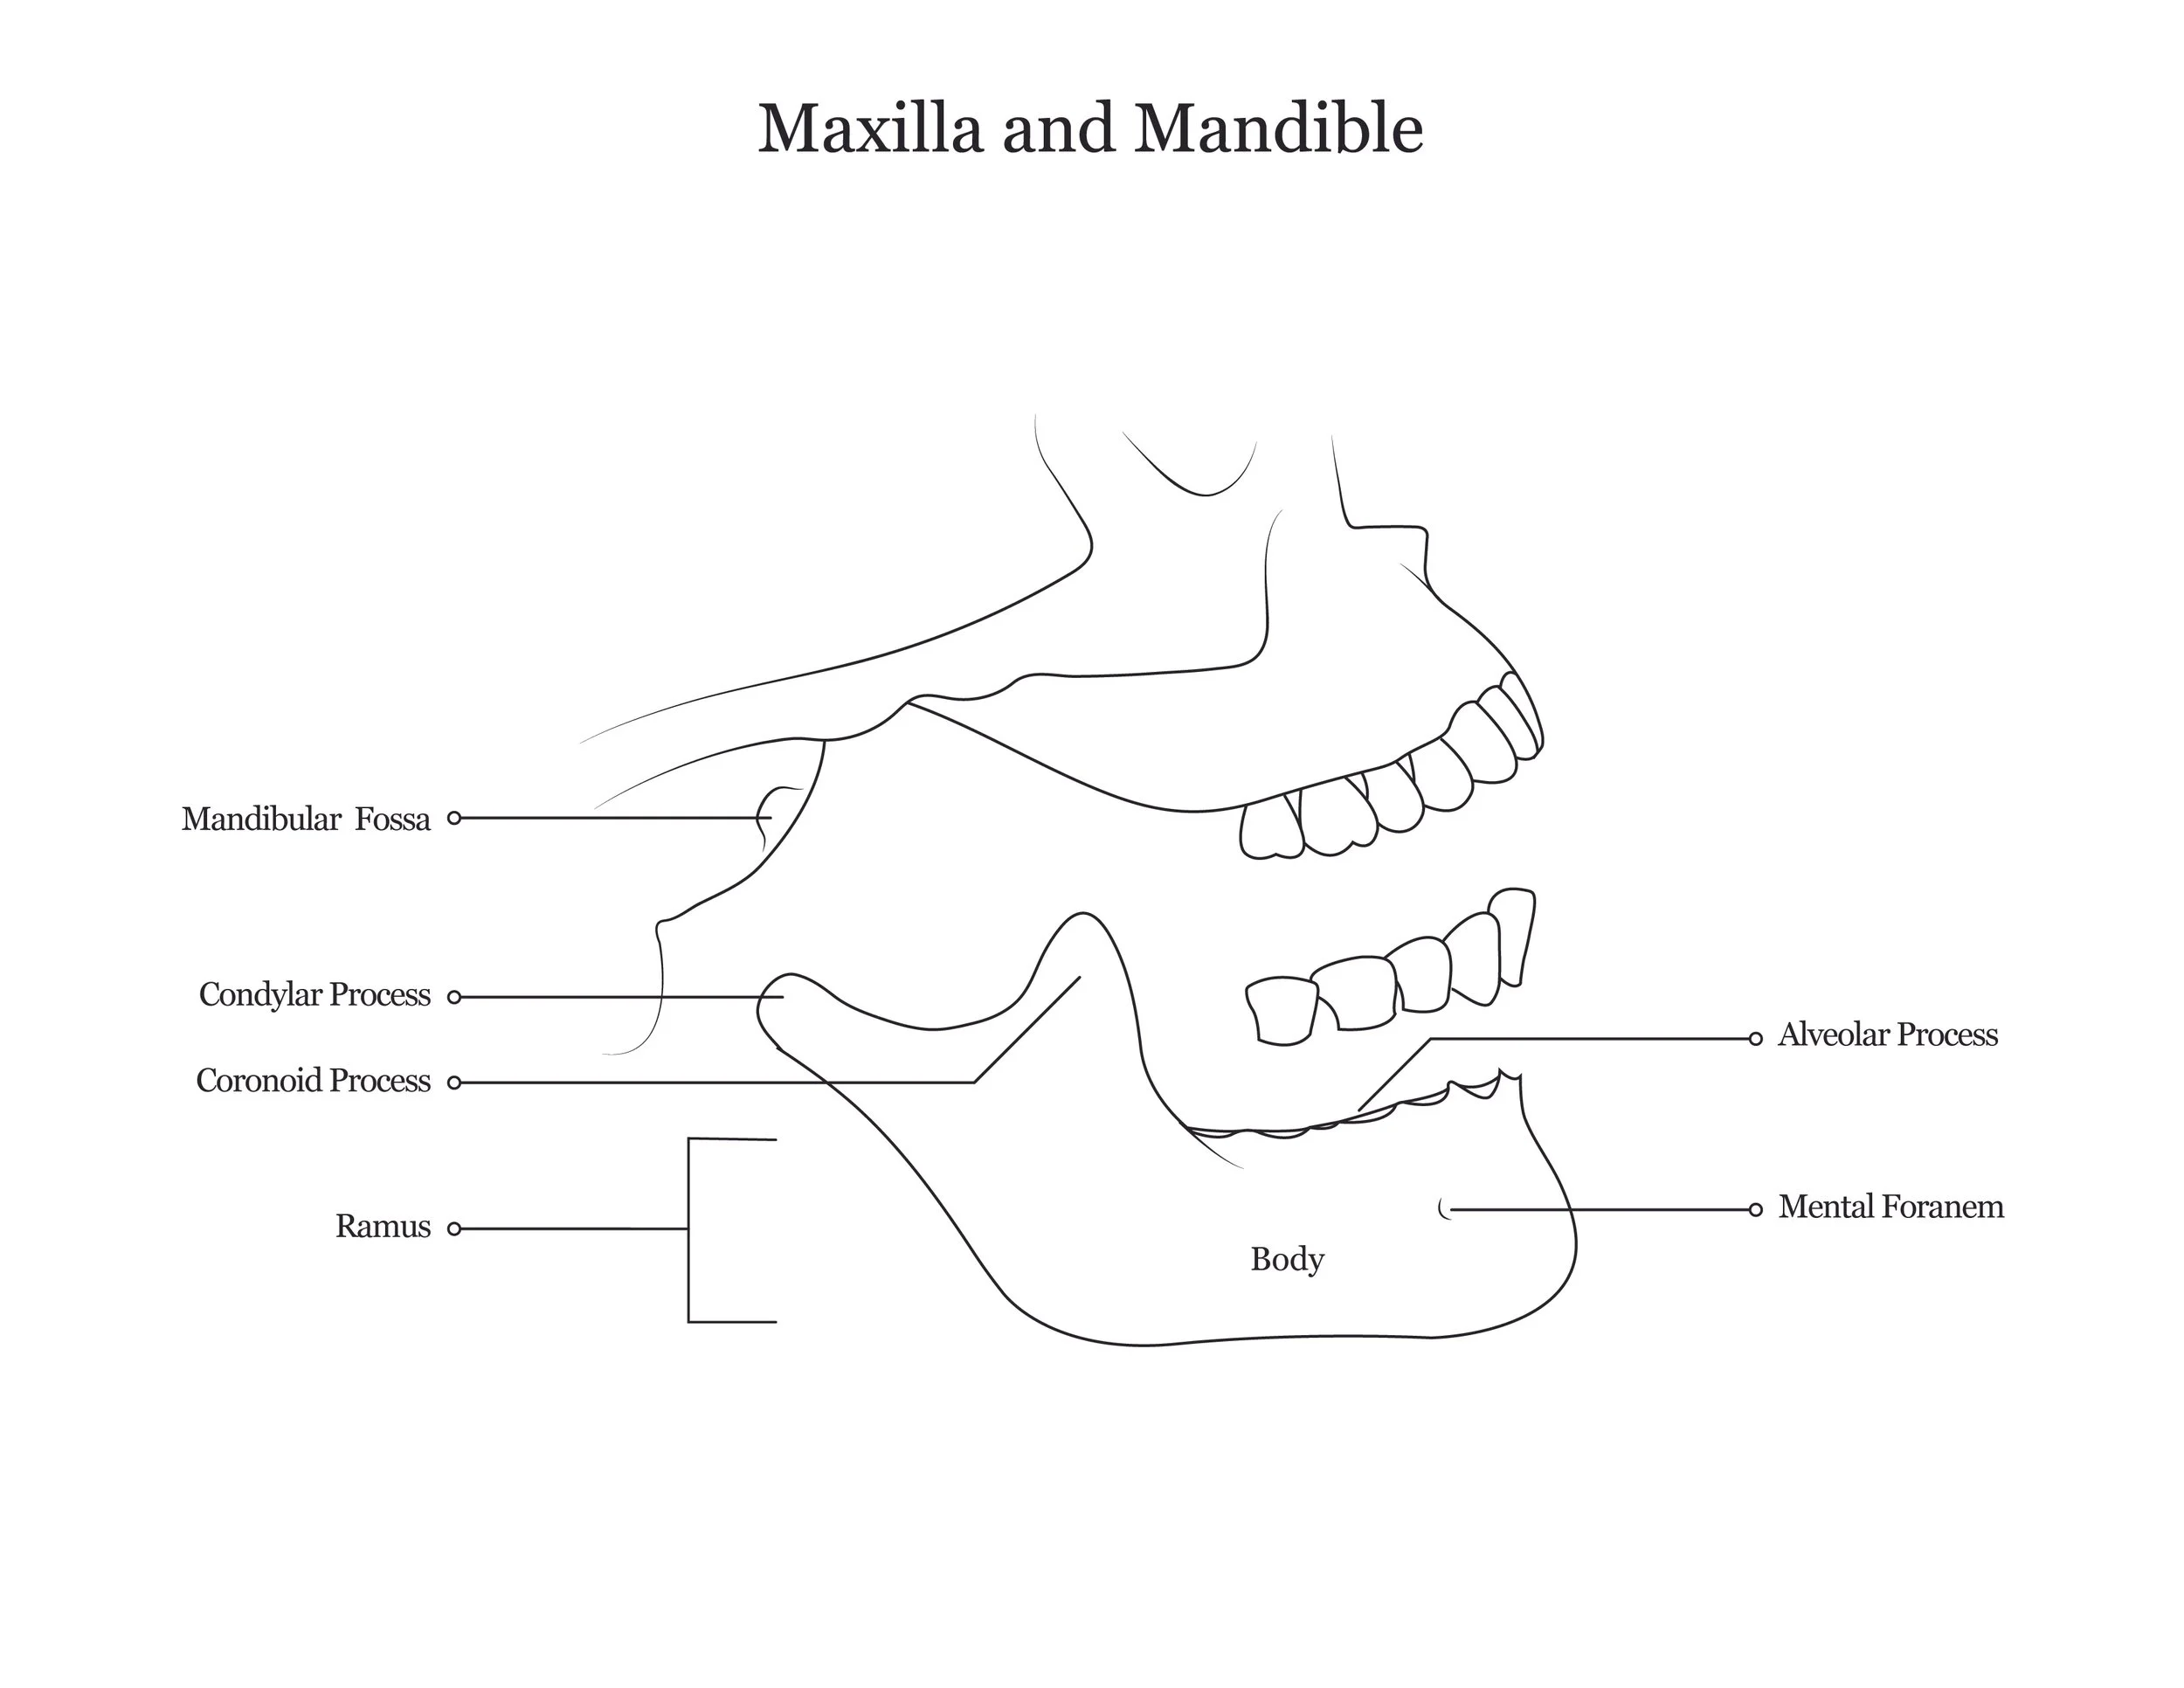

A series of anatomical illustrations created for Arcadia University’s Biology Department.

This project involved illustrating a series of diagrams for a cat dissection manual, focusing on skeletal and muscular anatomy. I consolidated multiple reference sources and firsthand specimen observation into a cohesive visual system for instructional use. Illustrations were refined iteratively to ensure anatomical accuracy, consistency, and clarity for students.